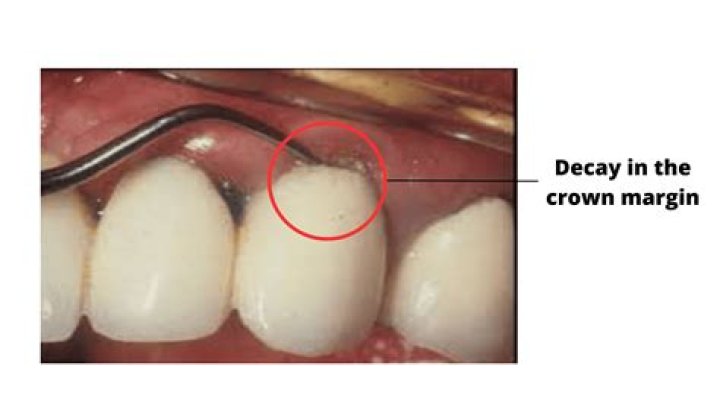

A crown is attached to a natural tooth by means of a crown base. As a result, decay can form on the crown’s periphery. Only by removing the old crown, removing the decay, and constructing a new one can you restore a crown that has decay around the edges.

Detecting the presence of rotting teeth beneath crowns. Cavities and decay may be difficult to detect if the affected area is small. Typically, an x-ray will be used by the dentist in order to make this discovery. It is up to him or her to determine if the teeth beneath are healthy or damaged.

A simple dental filling can be applied to the edge of a dental crown if the cavity was discovered early enough. Fillings, on the other hand, don’t have as strong a seal, so they’ll need to be monitored more closely.